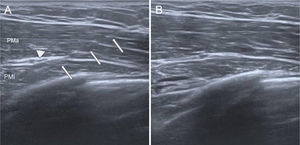

Infiltration. Using a 22 G needle, the puncture is performed under ultrasound guidance, with the drug being deposited first in the deepest layer and then in the more superficial ones. The content should be deposited intramuscularly, although a small amount may leak into the intermuscular plane due to the puncture itself (Fig. 2).

Figure 2.BT infiltration in the abdominal wall. (A) Musculature of the anterolateral abdominal wall, with the transverse muscle (T) difficult to visualise, located deep to the internal oblique (IO) and external oblique (EO), a characteristic finding in patients with abdominal wall weakness. (B) Infiltration process with a 22G needle, with the drug being deposited in the IO after the T has already been infiltrated; both appear thickened.

- 5

Technical considerations. These patients present with abdominal wall weakness and, in some cases, the muscle may be difficult to visualise, particularly the transverse muscle. Assistance may be requested to inject the drug while the operator handles the needle and guides the procedure with ultrasound, providing greater stability. A transversus abdominis plane (TAP) block can be administered beforehand to enhance patient comfort during the procedure.